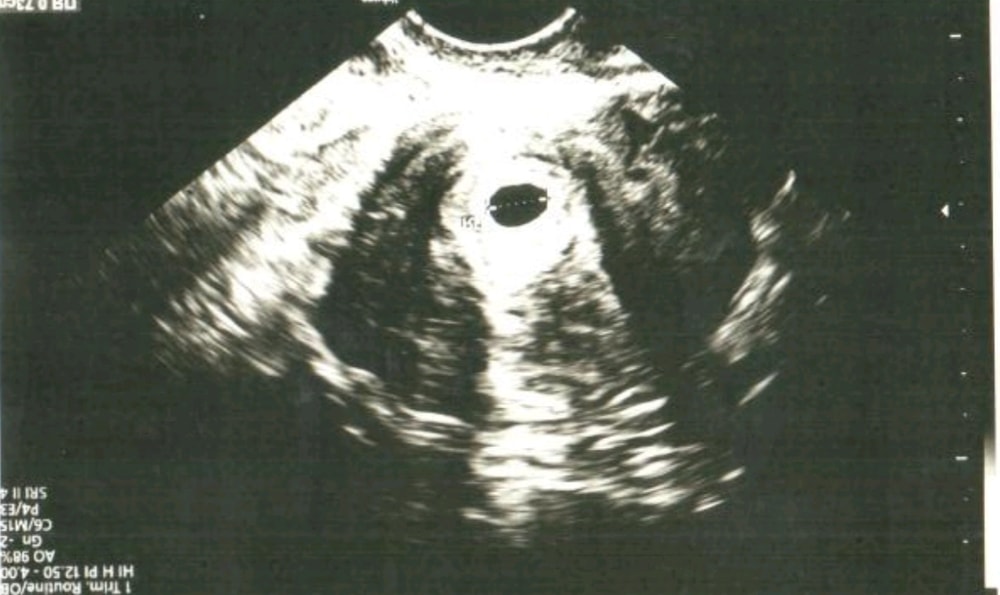

УЗИ на 21 дпп❤️❤️🥰,следующее через 10 дней🥰

Беременность маточная 😍 ,одно плодное яйцо❤️перенос был двух эмбриончиков❤️❤️.Моя крошка одна осталась со мной😘, но узистка говорит ещё рано точно говорить один или два, через 10 дней посмотрим эмбриончик❤️послушаем сердечко🤰Господи до сих пор не верю ,что беременная☺️ Срок акушерский 5,5 недель🤰